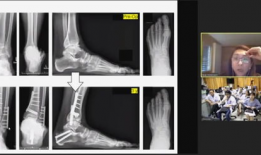

骨科视频,常见骨折与手术技巧全解析

亲爱的读者们,你是否曾因为关节疼痛而烦恼不已?又或者,你身边有没有朋友正在经历骨科疾病的困扰?今天,就让我带你走进一个全新的世界...

2025-12-14 53 -